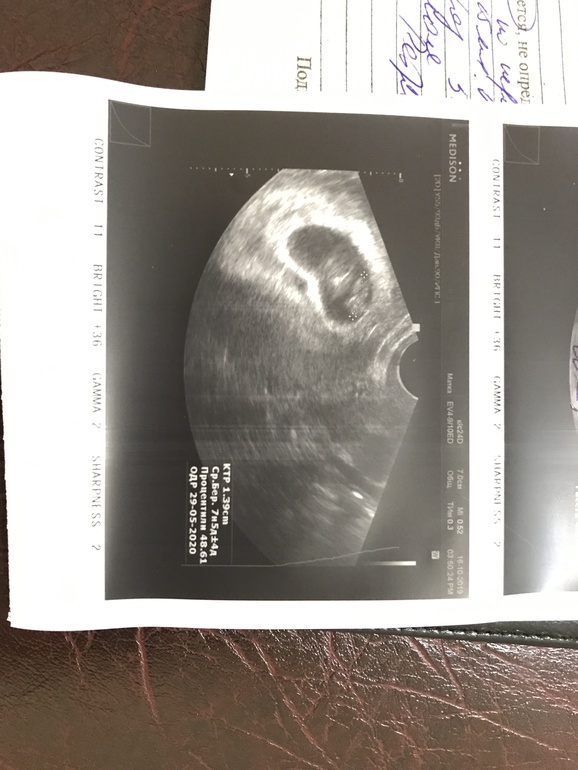

КТР, то есть размер эмбриона у вас почти 14 мм, то есть полтора см, оттуда же СБ + и ЧСС 158 уд. в минуту... Хорион по передней стенке в дне матки...